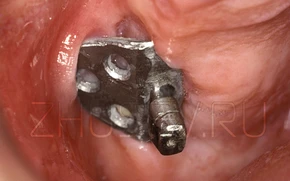

Посмотрите на данный пример. Вид имплантата действительно устрашающий. Это единственный из представленных ниже имплантатов не российская самоделка. Это американский имплантат Ramus Blade. Сразу понятно, что во всем мире путь имплантации был тернист!

Данная конструкция содержит внутренний винт, который при заворачивали раскрывал лепестки в нижней части имплантата. Так, как это бывает с обычным строительным дюбелем.